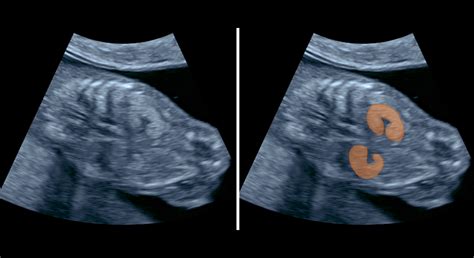

V 6. týždni hladina progesterónu prudko stúpa a ozývajú sa tehotenské nevoľnosti. Snažte sa ich zvládať tým, že budete jesť menšie porcie. Plod v 6. týždni meria asi 8 milimetrov a váži približne 1 gram. Srdiečko, kde sa tvoria komory, začína biť asi 100-130-krát za minútu. V 6. týždni tehotenstva vás možno čaká prvé ultrazvukové vyšetrenie. Prvýkrát tak budete môcť svoje dieťatko uvidieť, aj keď do podoby bábätka bude mať ešte veľmi ďaleko. Ak vás lekár na ultrazvukové vyšetrenie zatiaľ neodporučí, nezúfajte - dočkáte sa v 7. týždni.

V 7. týždni vaša maternica sa zväčšila približne do veľkosti citróna. Pravdepodobne pretrváva pocit únavy a môže sa objavovať vracanie. Pozornosť venujte starostlivosti o svoj chrup, ktorý môže počas tehotenstva trpieť. Drobné črty bábätka ako sú oči, nos, ústa a uši začínajú byť zreteľnejšie. Nervové bunky sa ďalej množia a vyvíjajú - formuje sa nervový systém. V tomto týždni sa už určite môžete tešiť na prvý ultrazvuk. Ten prebehne vaginálne - lekár skontroluje zväčšenie maternice a prekrvenie krčka maternice. Pri prehliadke vám môže byť zmeraný tlak, skontrolovaná hmotnosť a vyšetrený moč.

V 8. týždni stále môžu pretrvávať pocity na vracanie a nevoľnosť. Medzi najčastejšie tipy, ako si s nimi poradiť, patrí mať neustále niečo v žalúdku - snažte sa jesť menšie porcie častejšie počas dňa. Medzi ďalšie príznaky patria aj bolesti hlavy a zvýšená citlivosť na pachy. V priebehu tohto obdobia pravdepodobne zaznamenáte aj zvýšenú produkciu bieleho krémového výtoku z pošvy. Ten vzniká v dôsledku vyššej hladiny estrogénu a nie je dôvodom na obavy. V malých končatinách bábätka sa vyvíjajú nervy, kosti a svaly. Na končatinách, ktoré dosiaľ vyzerali ako pádielka, sa oddeľujú prsty. Bábätko sa začína hýbať - prvé pohyby začínajú približne v 7. až 8. týždni a sú viditeľné na ultrazvuku. Pohyby bábätka však pocítite až niekedy medzi 16. a 22. týždňom.

V 9. týždni vaše telo pracuje naplno, aby dodalo všetko potrebné vám aj vášmu bábätku. Doprajte si preto dostatok oddychu. Hormonálne výkyvy môžu spôsobovať tehotenské chute - dajte si, na čo máte chuť, ale vyberajte vždy čo najkvalitnejšiu variantu. Mnoho mamičiek na začiatku tehotenstva čelí aj páleniu záhy. Ak je to aj váš prípad, vyhnite sa sýteným nápojom, kofeínu, čokoláde, citrusovým plodom a šťavám, paradajkám, horčici, octu, mätovým výrobkom a spracovanému mäsu. Žalúdok vám môžu podráždiť tiež potraviny, ktoré sú tučné, korenisté, vyprážané alebo silne korenené. V tomto týždni sa vo vašom brušku deje veľa malých zázrakov a bábätko má vo svojom vývoji naozaj plné ruky práce. Vaše bábätko teraz meria okolo 1,7-2,2 centimetra a váži cca 2 gramy. Má už všetky základné časti tela, vrátane lakťov a kolien. Sú vytvorené základy pre dvadsať mliečnych zubov, vytvárajú sa slzné žľazy a začína aj tvorba slzného kanálika. Na tvári sa mu vytvoril horný pysk, nos a očné viečka. V tomto období sa tiež formujú pohlavné orgány - pohlavie bábätka však ešte nemožno určiť. Na ultrazvuku je zreteľne počuť srdiečko plodu.

V 12. týždni vaše telo sa naplno pripravuje na celé tehotenstvo. To sa prejavuje nielen náhlymi zmenami nálad, ale aj zväčšením prsníkov a tmavnutím bradaviek. U niektorých budúcich mamičiek sa tiež objavujú pigmentové škvrny v oblasti tváre a krku. Vytvoriť sa môže aj pigmentová čiara označovaná niekedy ako tzv. linea negra, ktorá sa tiahne od pupka smerom nadol. Bábätko na konci prvého trimestra naozaj rastie „ako z vody“. V tomto období by ste už mali mať za sebou jedno ultrazvukové vyšetrenie, počas ktorého sa určil počet plodov, ich vitalita a rozmery. Prvé veľké ultrazvukové vyšetrenie väčšinou prebieha až v 13. týždni.

13. týždňom končí prvý trimester - najkrehšie obdobie celého tehotenstva, kedy je najvyššie riziko spontánneho potratu. Väčšina budúcich mamičiek tak vstupuje do 2. trimestra. Narodenie bábätka je ešte ďaleko, vaše prsia sa však už začínajú pripravovať na dojčenie. Čoskoro začnú produkovať žltú tekutinu - mledzivo/kolostrum. Bábätko prehĺta plodovú vodu a vylučuje moč. Prehĺtanie plodovej vody spôsobuje aj tvorbu mekónia - čiernej lepkavej látky, ktorá sa hromadí v črevách bábätka a je jeho prvým „kakaním“. V tomto týždni vás čaká prvé veľké ultrazvukové vyšetrenie. Jeho dĺžka sa odvíja od toho, akú pozíciu vaše bábätko zaujme. V tomto období budete tiež absolvovať krvné testy, ktoré spolu s výsledkami z ultrazvuku slúžia na vylúčenie genetických vád ako je napr. Downov syndróm. Na tomto ultrazvuku sa lekár zameria najmä na genetické vady. Prvý trimester je zázračným obdobím plným očakávaní, ale aj strachu. Vaše telo sa začína pomaly pripravovať na celé tehotenstvo a príchod bábätka. Preto si doprajte dostatok oddychu a predovšetkým kvalitnú stravu, ktorá ovplyvňuje správny vývoj vášho bábätka.

Počas prvej návštevy u gynekológa sa tehotenstvo oficiálne potvrdí. Odporúča sa objednať na prvé tehotenské vyšetrenie medzi 6. - 8. týždňom. Tehotenský preukaz sa vystavuje medzi 7. - 11. týždňom tehotenstva (cca na 2. návšteve v poradni pre tehotné). Odporúča sa nosiť ho vždy pri sebe. Pri prvých odberoch sa zisťuje vaša krvná skupina a Rh faktor, vrátane prítomnosti antierytrocytárnych protilátok. Prvý ultrazvuk potvrdí vitalitu bábätka, určí gestačný vek aj početnosť tehotenstva. Kombinovaný prvotrimestrálny skríning (odber krvi a ultrazvuk) pomáha odhaliť najčastejšie genetické ochorenia ako Downov, Edwardsov či Patauov syndróm. Pozitívny výsledok ešte neznamená postihnutie. Je však signálom na ďalšie vyšetrenia, ktoré môžu ochorenie potvrdiť alebo vylúčiť. Prvotrimestrálny screening sa vykonáva medzi 10. - 13. týždňom tehotenstva a je dôležitým vyšetrením na včasné odhalenie genetických porôch a vývojových abnormalít plodu. Výsledky týchto vyšetrení spoločne určujú riziko genetických ochorení, ako je Downov syndróm. Tiež určujú presný vek plodu, počet plodov, srdcovú činnosť, merajú hrúbku šije a nosovú kostičku a kontrolujú sa zárodky všetkých existujúcich orgánov.